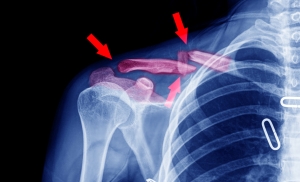

Broken Collarbone

Перелом ключицы